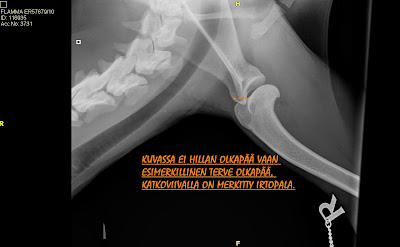

Nappasin jostain kuvan islanninlammaskoiran oikeasta olkapäästä ja merkitsin katkoviivalla irtopalan rajan. tässä kohtaahan pentuikäisellä koiralla sijaitsee kasvuviiva, jonka olisi kuitenkin pitänyt sulkeutua siihen mennessä kun Hilla törmäsi. Voi kuitenkin olla että se on vielä ollut hieman avonainen ja heikko, joka on aiheuttanut palan irtoamisen yhtetettynä kovaan törmäykseen. Arvelimme, että todennäköisesti peräkärryn aisaan sillon kerran pimeänä syksy iltana.

Alla oleva kuva on napattu jostain netistä, jossa on islanninlammaskoiran terve oikeanpuoleinen olkanivel. Merkitsin kuvaan suurinpiirtein sen kohdan mistä irtopala on lähtenyt. Edelleenkin saa vain ihmetellä miten se ei ole voinut olla kipeä???